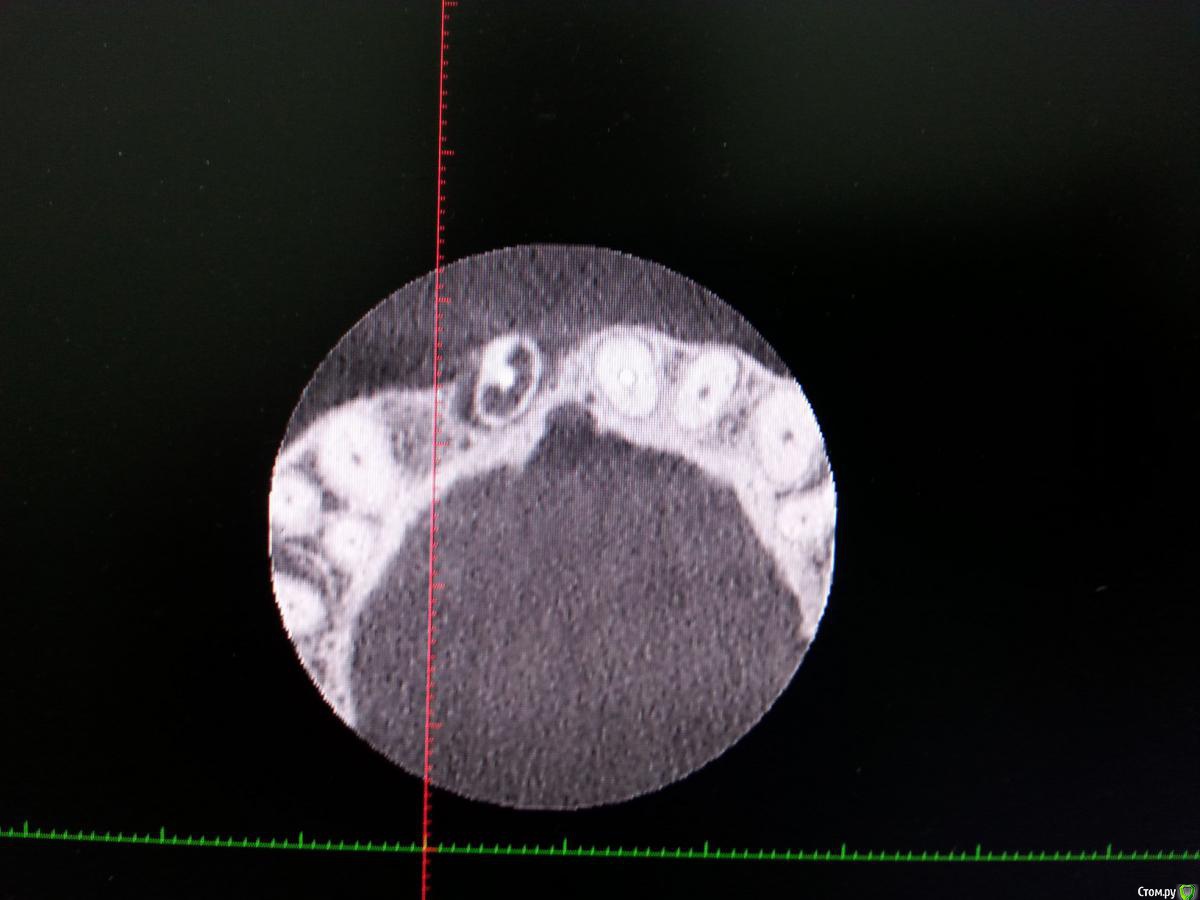

red_butler Опубликовано 30 декабря, 2016 Поделиться Опубликовано 30 декабря, 2016 У 12 толщина кости 4,6, предлагают имплантировать. Толщины достаточно? покажите срезы Кт Ссылка на комментарий

Zamber Опубликовано 30 декабря, 2016 Автор Поделиться Опубликовано 30 декабря, 2016 покажите срезы Кт Кажется, этот Ссылка на комментарий

red_butler Опубликовано 30 декабря, 2016 Поделиться Опубликовано 30 декабря, 2016 Да здесь ситуация лучше. Ссылка на комментарий